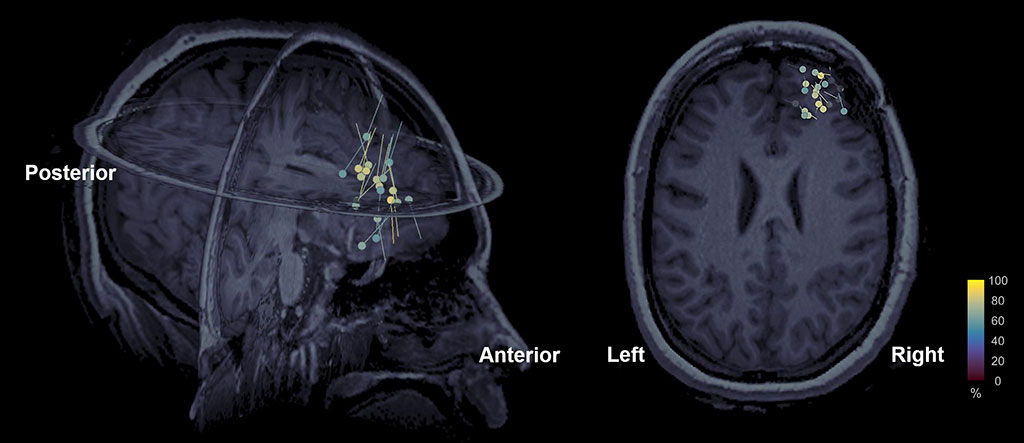

HD-EEG is usually combined with a magnetic resonance imaging (MRI) to get what is called electric source imaging (ESI), which offers precise localization (spatial location) of brain activity (as dipoles) millisecond by millisecond. ESI is often used in clinical practice for the precise localization of epileptogenic tissue in patients with epilepsy who are unable to control their seizures with seizure medications (Fig. 2). Derivatives of the HD-EEG technique include evoked potentials, which involves averaging the EEG activity time-locked to the presentation of a stimulus of some sort (visual, somatosensory, or auditory) or a child’s response (motor). Event-related potentials (ERPs) refer to averaged EEG responses that are time-locked to more complex processing of stimuli. This technique is used for the localization of eloquent areas in the human brain during presurgical mapping as well as to help us better understand the function of the human brain and to monitor functional brain plasticity in response to rehabilitation.

Figure 2: Electric source imaging in presurgical evaluation of children with epilepsy. Source localization findings with ESI (256 channels HD-EEG) from a 12-year-old girl with medically refractory epilepsy. Localization is performed using equivalent current dipoles. A tight cluster of dipoles was found in the right frontal areas near the previous surgical resection that was partially beneficial to the child. These findings indicate a secondary spot of epileptogenic activity that should be resected in order for the child to be seizure free.